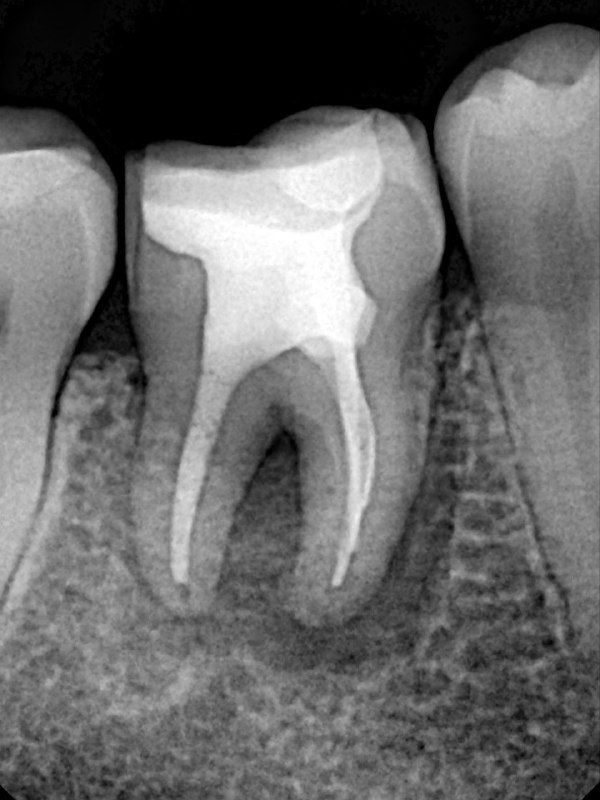

- 1) Обязательно провожу хорошую изоляцию, чтобы была видна полностью коронка зуба. Это важно для создания полости зуба, так как контуры пульпарной камеры повторяют внешние контуры коронки зуба.

- 4)При препарировании каналов стараюсь придерживаться миниинвазивной концепции: в каналах пошире - до чистых дентинных опилок (25,30.04), в тонких корешках может быть и 20.04. за счёт использования активации ирригационных растворов, можно уменьшить размер препарирования.

- 7) Пломбирую вертикальной компакцией гуттаперчи, в то же посещение делаю билдап. А вот коронкой зуб покрывает уже через 6 мес после реколла.